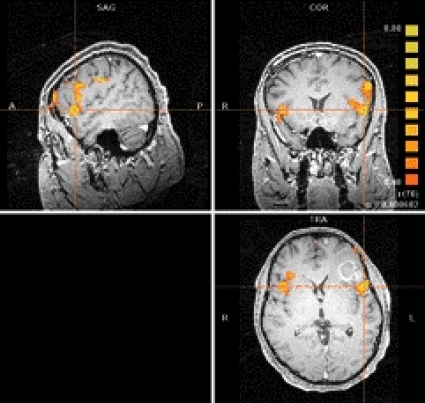

Funktionell MR (fMRI). fMRI kan helt icke-invasivt påvisa aktivering i hjärnbarken vid motorisk aktivitet, tex vid fingerrörelse eller vid sensorisk stimulering. Man kan även påvisa aktivitet då patienten/försökspersonen tänker på ord, vilket kan lokalisera språkcentrum. Metoden används också mycket för kognitiva studier. Preoperativ fMRI med bildtagning som täcker hela hjärnan kan användas för att kartlägga lokalisationen av viktiga funktioner i hjärnbarken hos patienter med hjärntumörer och andra lesioner, vilket är till nytta för den preoperativa planeringen (Figur 4). Den ökade känsligheten för signalskillnader vid aktivering jämfört med vila vid höga fältstyrkor, orsakad av blodflödesförändringar med ändrad halt av deoxihemoglobin, ger mer tillförlitlig lokalisation av hjärnfunktion och kortare undersökningstider [10].